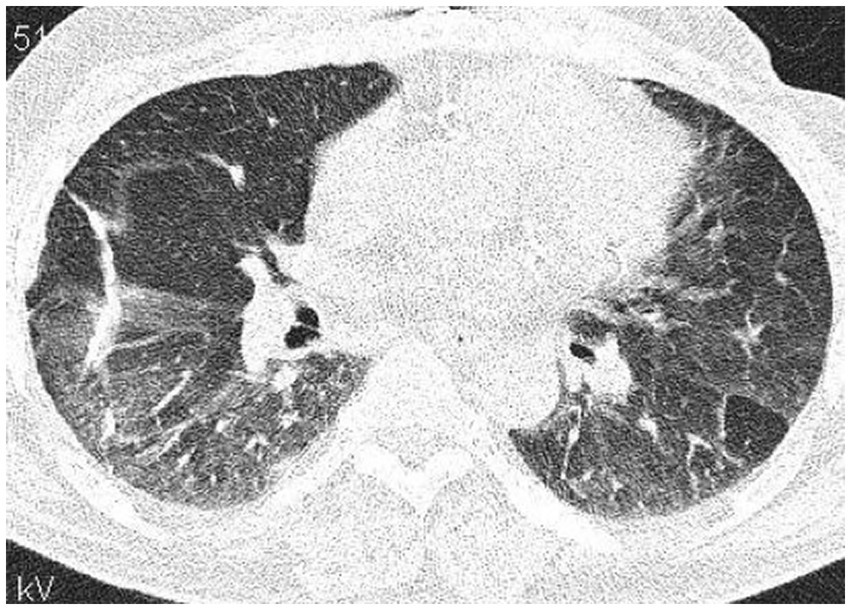

High-resolution computed tomography (HRCT) is the gold standard in the evaluation of OP. It reveals multifocal areas of consolidation, often with a characteristic air bronchogram. Additionally, patchy alveolar consolidations, nodules, areas of ground glass opacity, perilobular infiltrations, bronchial wall thickening, and reticular fibrous changes may be present in peripheral parts of both lungs. Thickening around areas of ground glass opacity with an “atoll” or “crazy-paving” pattern may also be present, although it is less common. Additionally, nodular lesions, pleural thickening, and rarely enlargement of hilar and mediastinal lymph nodes, are present; emphysema or pleural effusion may also be observed (28–40). Honeycomb-type lesions are not in the spectrum of pulmonary changes observed in COP but might be evident in patients who exhibit interstitial pulmonary fibrosis with a component of OP (Figures 2–6).

High resolution computed tomography scan of a patient with SOP in the course of dermatomyositis. In both lungs evidence of GGO with patchy distribution and parenchymal banding with “arcade” sign typical of OP. Status post lung biopsy on the right side.